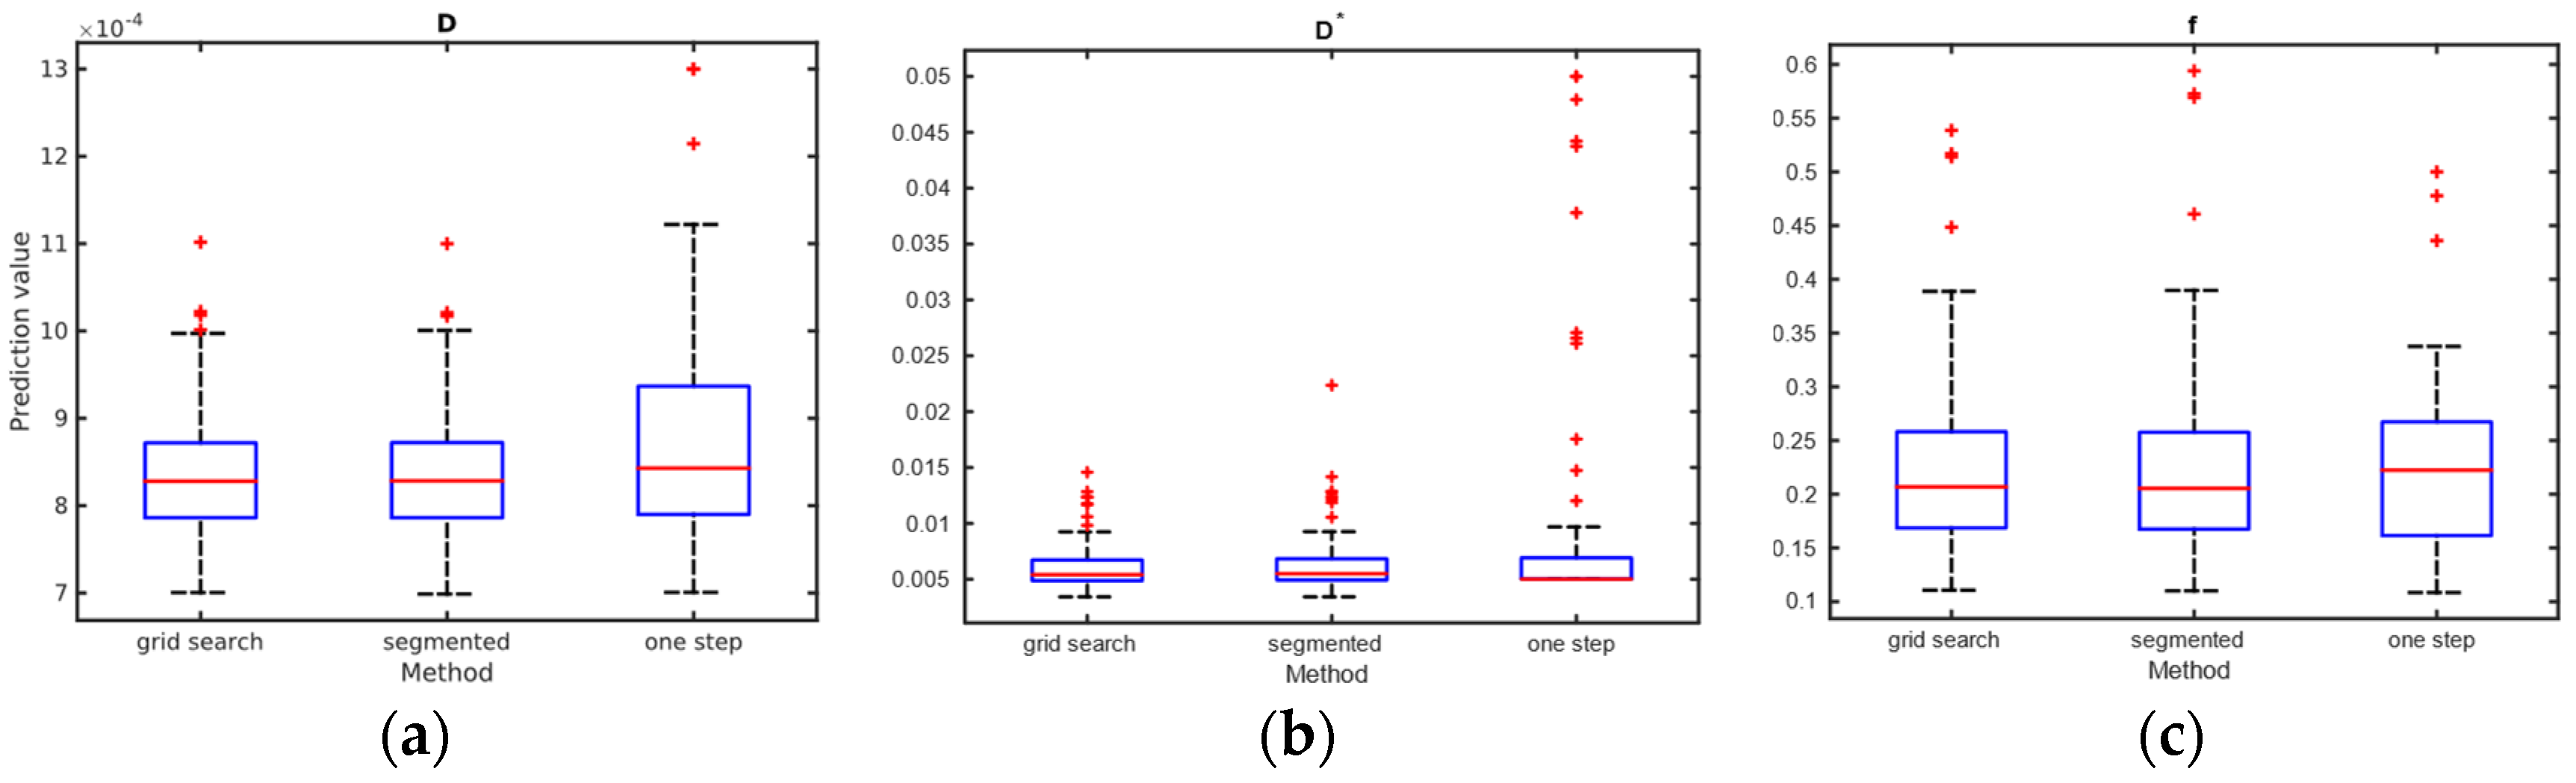

3.3. Results from Study

3.3.2. Calculation of IVIM Parameters